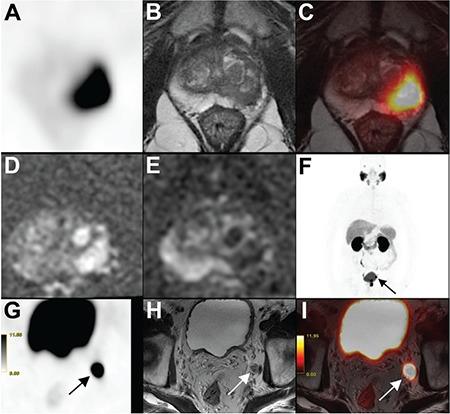

Gallium-68 (Ga-68) prostate specific membrane antigen (PSMA) positron emission tomography (PET) has been shown to be more accurate than multiparametric prostate magnetic resonance imaging (MRI) in detection of primary prostate lesions. Using hybrid PET/MRI we aim to detect the correlation between SUV and apparent diffusion coefficient (ADC) in primary prostate lesions and to assess their prognostic value in detection of lymph node (LN) metastasis.

Twenty-six patients, who were diagnosed as having prostate cancer with biopsy and underwent Ga-68 PSMA PET/MRI together with biparametric prostate MRI (bpMRI) were included. SUV, SUV and ADC were recorded for index lesions drawing a region of interest (ROI) of 1 cm around the pixel with the highest SUV (ROI-1) and another ROI following borders of prostate tumor detected by bpMRI (ROI-2). Presence of LN metastasis was recorded according to PSMA PET/MRI

SUV was inversely correlated with ADC (ROI-1: p=0.010; ROI-2: p=0.017 for b=800). SUV and SUV were both higher in patients with LN metastasis and ADC was lower in patients with LN metastasis for ROI-1. SUV cut-off value of 19.8 for ROI-1 and 20.9 for ROI-2 had sensitivity and specificity of 77.8% and 76.5%, respectively for detection of LN metastasis, whereas ADC (b=800) cut-off value of 0.92x10 mm/s had sensitivity and specificity of 87.5% and 76.5%, respectively. SUV/ADC (b=800) ratio increased the sensitivity and specificity to 100% and 82.4%, respectively.

SUV and ADC values are inversely correlated in primary prostate lesions and the combined use of both values increases the diagnostic accuracy of hybrid PET/MRI in the detection of primary prostate lesions.